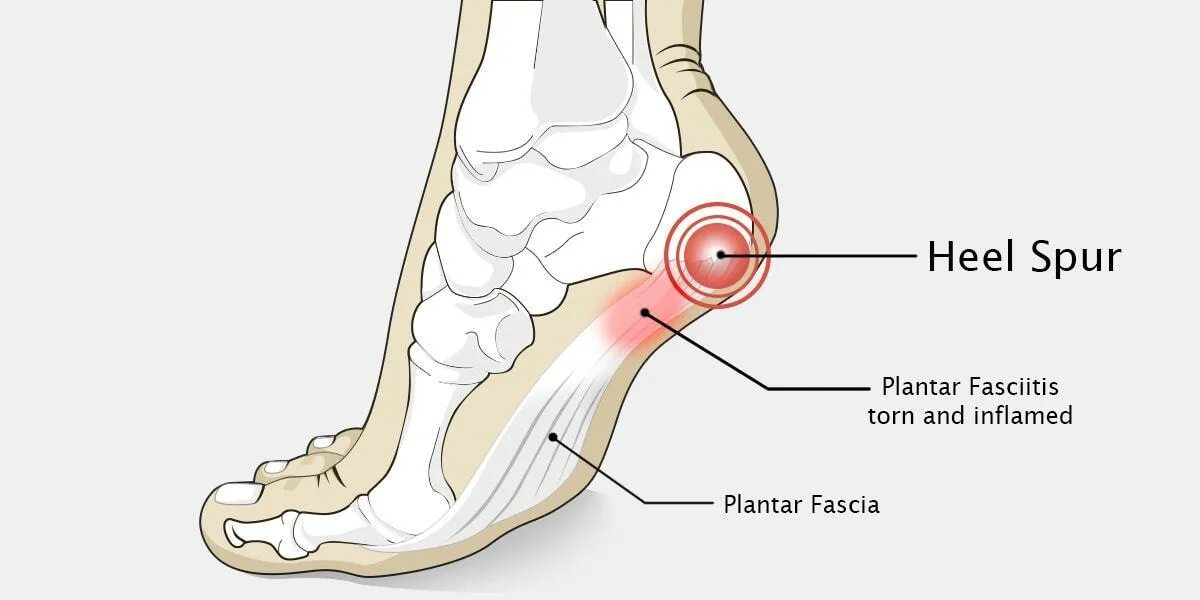

Пяточный фасцит